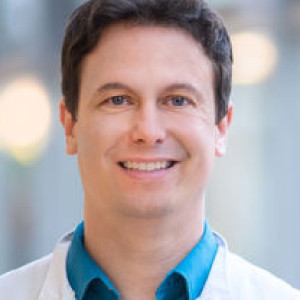

Experte

Prof. Dr. med. Benjamin Meder ist stellvertretender Ärztlicher Direktor der Klinik für Kardiologie, Angiologie und Pneumologie und Leiter des Instituts für Cardiomyopathien Heidelberg sowie des Herzkatheter-Bereichs. Zudem führt er das Molekulargenetische Labor für funktionelle Molekulargenetik und translationale Biotechnologie. Sein Fokus liegt auf der interventionellen Kardiologie und der Erforschung genetisch bedingter Kardiomyopathien.